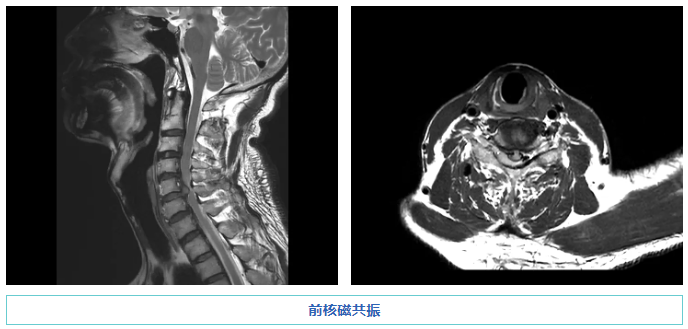

茂名市人民医院脊柱外科二区主任赵斌修接诊了伍先生,并为他完善了相关检查:核磁共振检查显示其颈椎有一个巨大的椎间盘突出,神经受到严重压迫。赵斌修主任团队在进行了详细的病例讨论和评估以及与家属充分沟通后,决定在显微镜的辅助下采用国内先进技术对患者施行微创脊柱手术治疗。